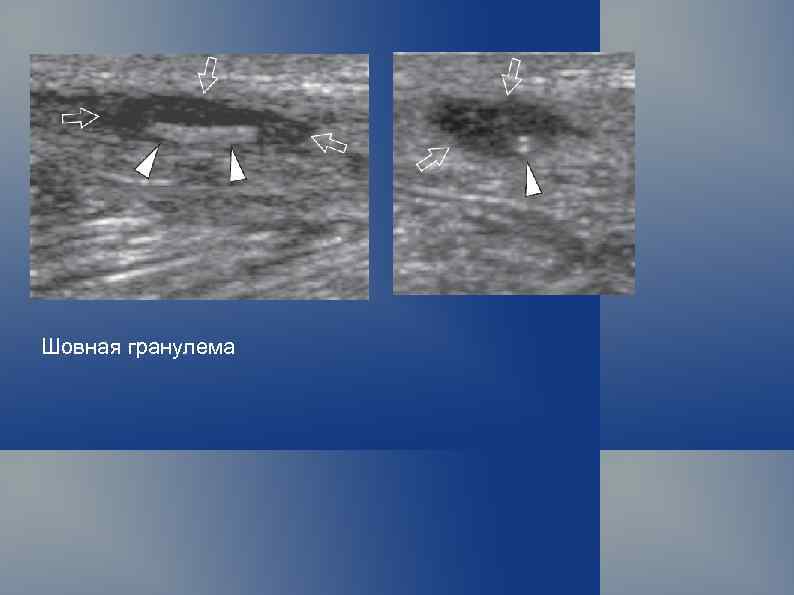

Шовная гранулема

Шовная гранулема